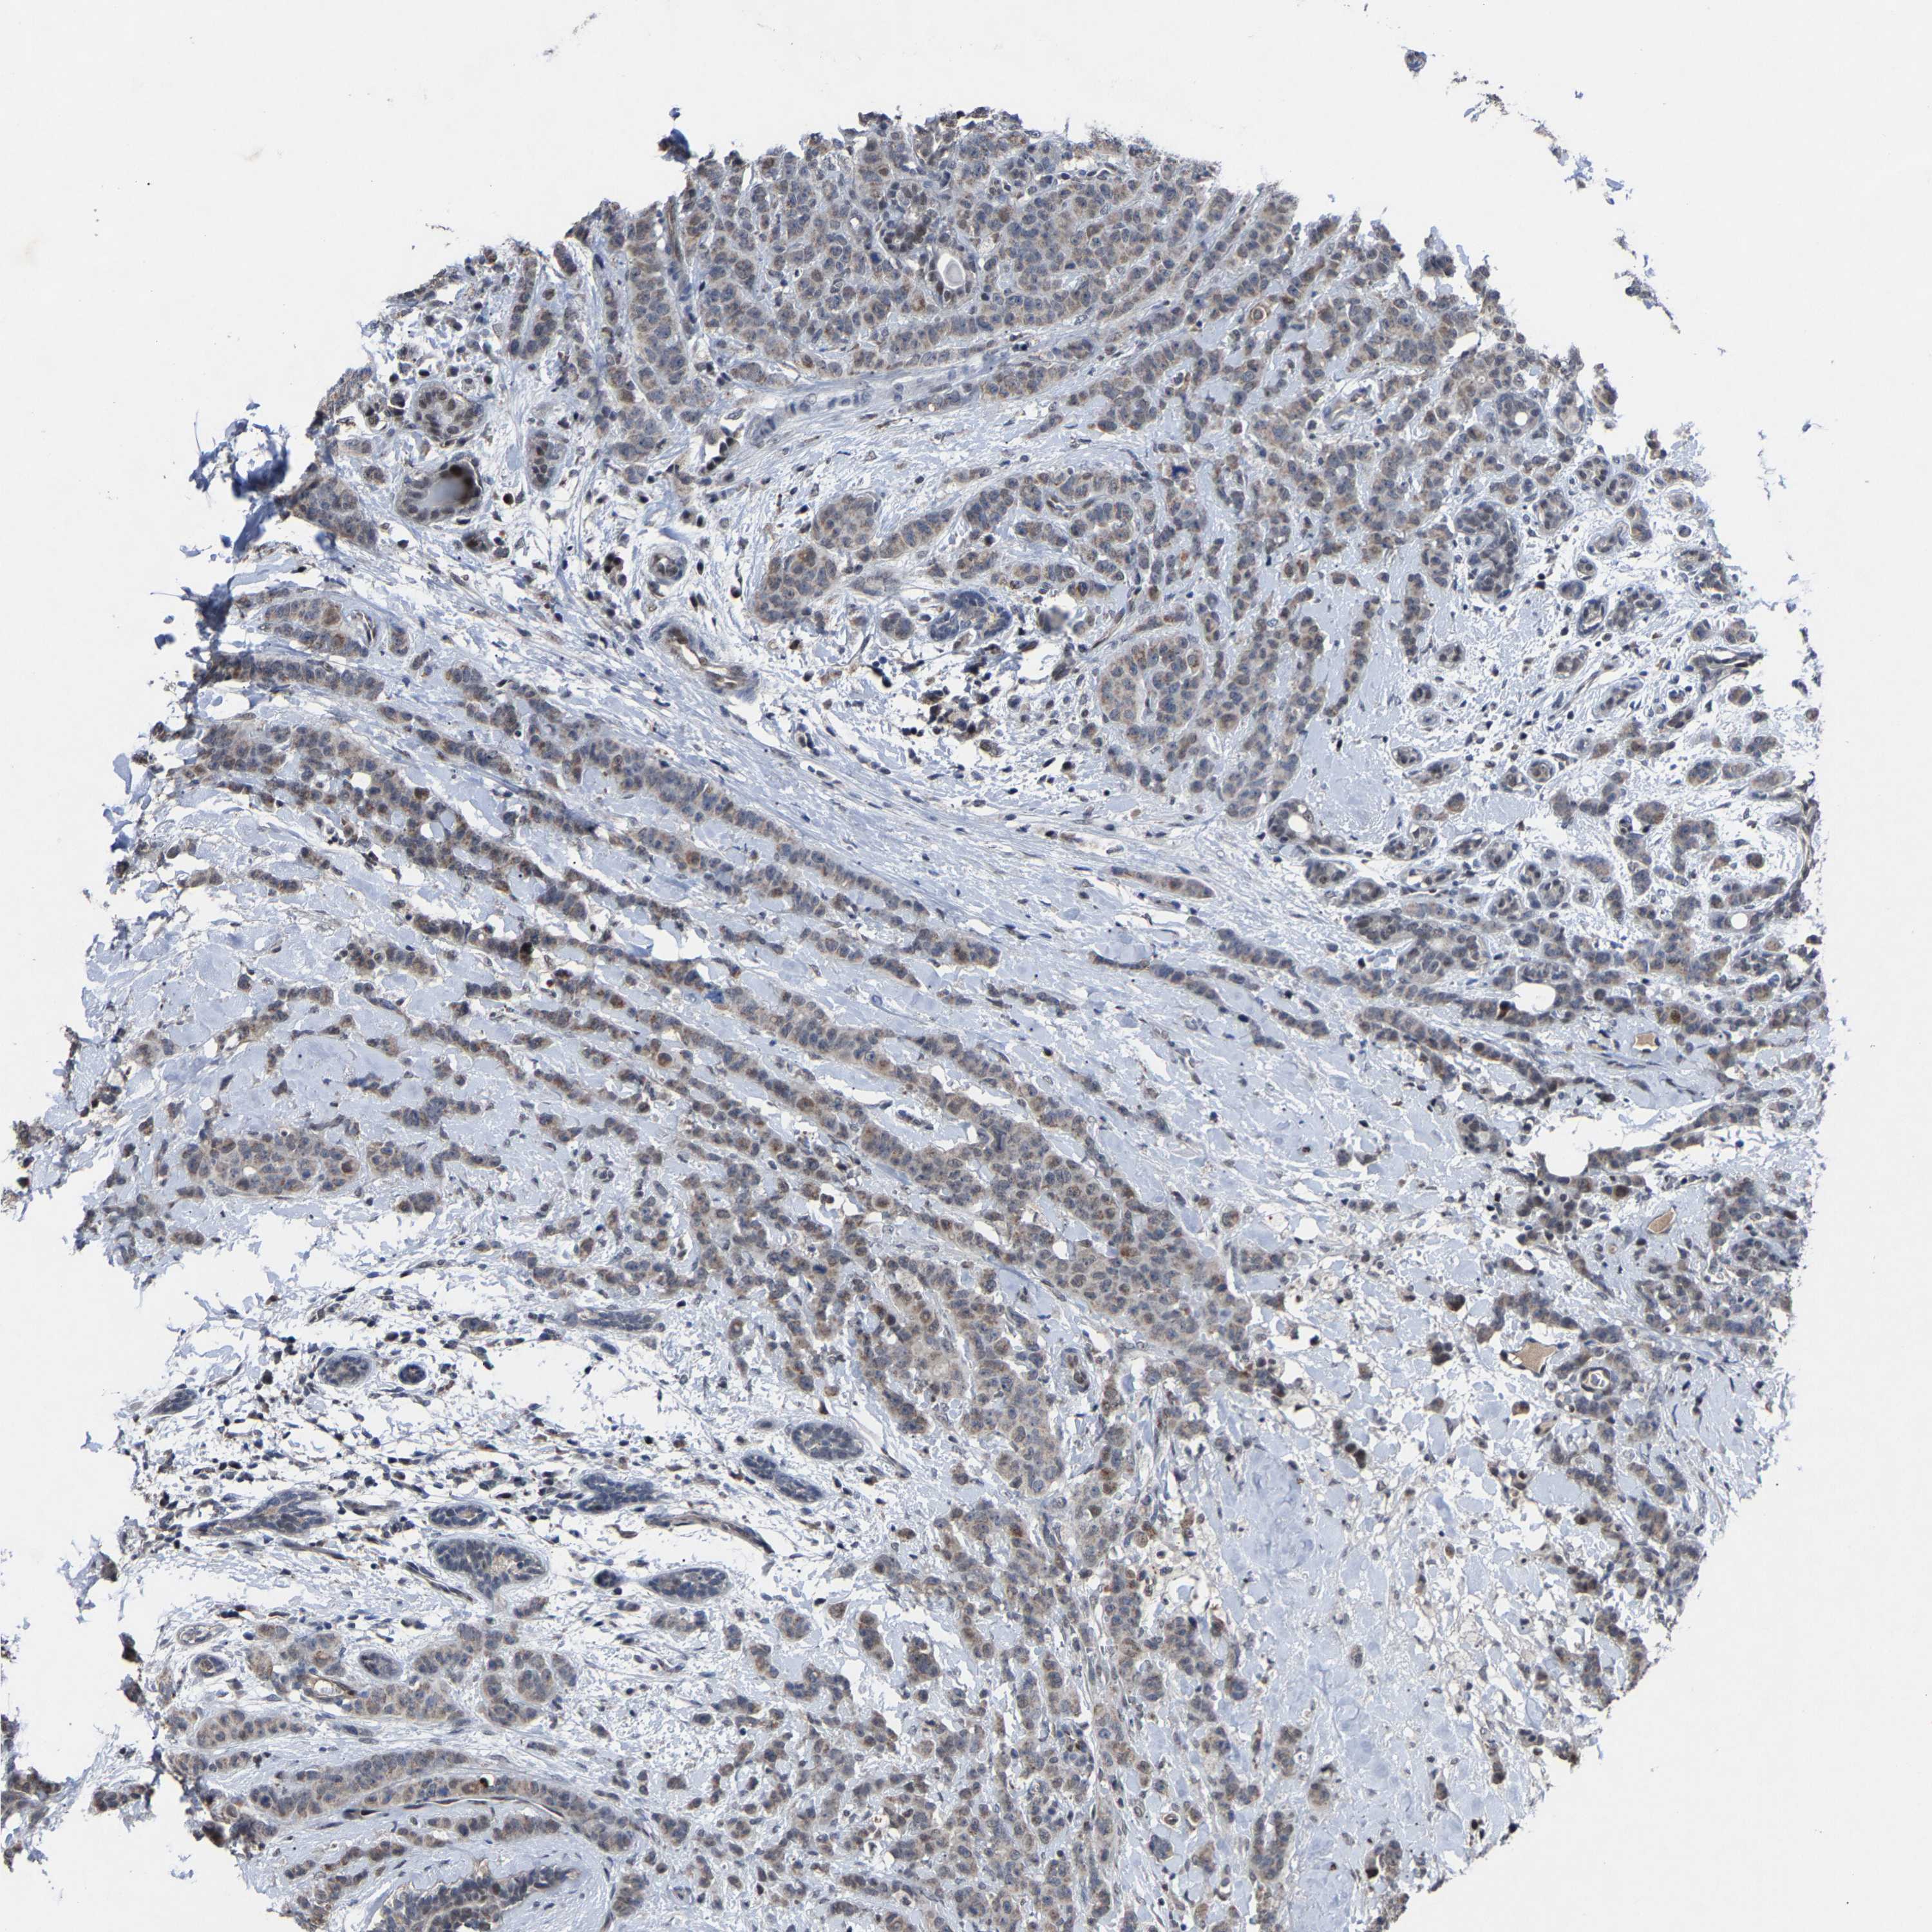

CANCER BREAST CANCER Show tissue menu

BRCA TCGA BRCA VALIDATION PROTEIN EXPRESSION

Breast cancer

Human cancer